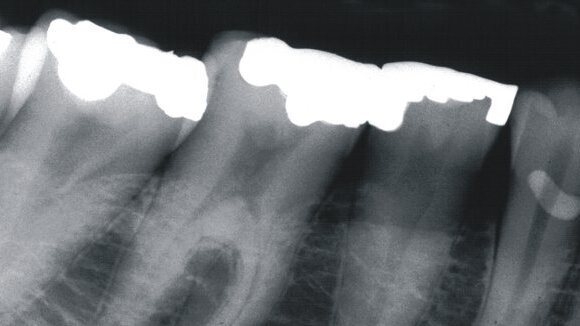

Les chercheurs de Göteborg ont poursuivi cette recherche avec une nouvelle étude qui démontre qu'il est possible d'utiliser des radiographies dentaires pour enquêter sur la structure osseuse de la mâchoire inférieure, qui permet aux médecins de prévoir le risque de fractures dans l'avenir.

"Nous avons découvert qu’une structure osseuse raréfiée dans la mâchoire inférieure à la mi-vie est directement liée au risque de fractures dans d'autres parties du corps plus tard dans la vie", a déclaré le professeur Lauren Lissner, chercheur à l'Institut de médecine de la Sahlgrenska Academy.

L'étude a constaté que la structure osseuse de la mâchoire était raréfiée pour environ 20 pour cent des participantes âgées de 38 à 54 ans lorsque le premier examen a été effectué, et que ces participantes ont été exposées à un risque significativement plus élevé de fractures.

"Les radiographies dentaires contiennent de nombreuses informations sur la structure osseuse", a déclaré Grethe Jonasson, chercheur au Centre de recherche de la fonction publique dentaire en Västra Götaland, qui a initié l'étude des fractures. "En analysant ces images, les dentistes peuvent identifier les personnes qui ont le plus de risque de fractures, bien avant la première fracture."